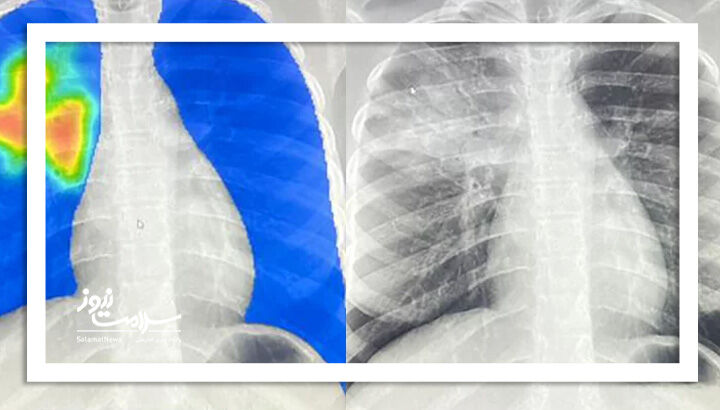

در مالی، اپراتورهایی که پزشک نیستند اما آموزش دیدهاند، تصاویر اشعه ایکس را گرفته و به کمک نرمافزارهای هوش مصنوعی تفسیر میکنند. اگر بخشهایی از ریه در تصویر قرمز رنگ شود، نمونه خلط برای تأیید نهایی به آزمایشگاه فرستاده میشود. این روش نهتنها زمان تشخیص را کاهش داده بلکه نیاز به جمعآوری نمونههای خلط را تقریباً به نصف رسانده است.

به گزارش سلامت نیوز به نقل از مدرن مد در کشورهایی مانند مالی و نیجریه، نرمافزارهای هوش مصنوعی با تحلیل تصاویر اشعه ایکس در چند ثانیه نواحی مشکوک به عفونت را مشخص میکنند — حتی در مراکزی که هیچ پزشک متخصصی حضور ندارد. این فناوری زمان تشخیص را از چند هفته به چند ثانیه کاهش داده و نیاز به آزمایشهای طولانی را به حداقل رسانده است.